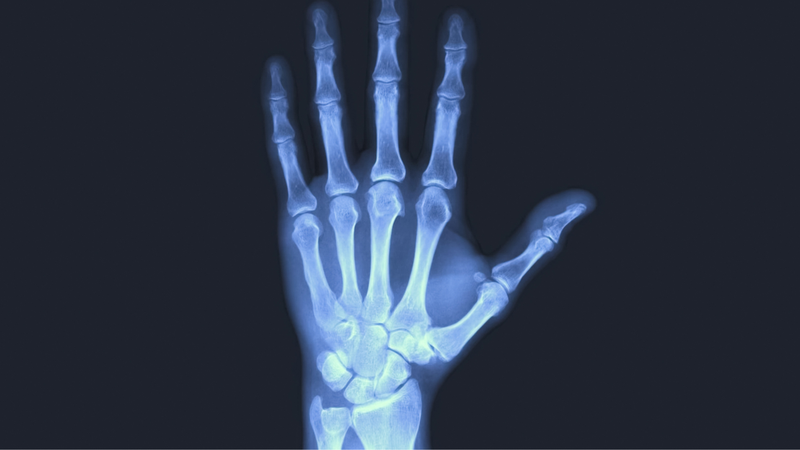

Gãy xương ngón tay thường gây đau dữ dội và sưng tấy kéo dài từ vài giờ đến nhiều ngày. Ngược lại, bong gân ngón tay cũng gây đau nhưng mức độ nhẹ hơn. Bác sĩ có thể phân biệt hai tình trạng này thông qua thăm khám trực tiếp, hỏi về triệu chứng và chụp X-quang xương ngón tay.

Bác sĩ chẩn đoán bong gân ngón tay thông qua việc thăm khám trực tiếp, chụp X-quang để loại trừ gãy xương, và chụp cộng hưởng từ (MRI) nhằm đánh giá mức độ tổn thương của dây chằng. Dựa vào tình trạng cụ thể, bác sĩ sẽ đề xuất các phương pháp điều trị phù hợp như sau: